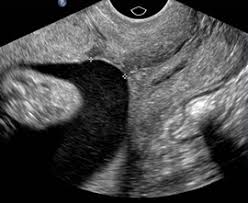

The placenta is the part that affects the uterine wall and serves as a supplier of oxygen and nutrients to the fetus in the womb. Normally, the placenta attaches to the side or top of the uterus. However, in the case of Placenta Previa, the placenta attaches to the bottom so as to cover part or all of the cervix. The closing of this birth canal does not allow the baby to be born normally, because the placenta that was hit by the baby will rupture and cause bleeding. Cesarean delivery (sc) is a way to prevent and minimize bleeding.

In early pregnancy, the placenta is located at the bottom of the uterine wall. As the pregnancy age increases, the fetus and uterus become larger. The size of the enlarged uterus makes the placenta attracted and shifts to the upper part of the uterine wall. If the gestational age has entered the third trimester but the placenta remains at the bottom of the cervix, this condition is called Previa.